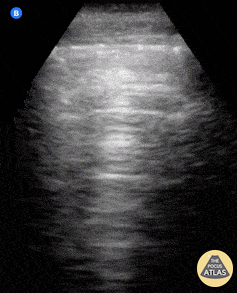

📈 Les Signes Dynamiques au Mode M

Le mode M (temps-mouvement) permet de visualiser les mouvements pleuraux dans le temps.

Signe du « bord de mer »

• Aspect de vagues horizontales au-dessus de la plèvre (paroi) et de texture granuleuse en dessous (poumon en mouvement).

• Indique un glissement pleural présent → poumon ventilé.